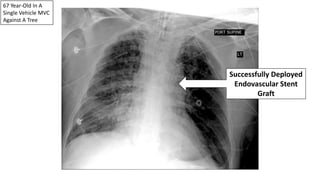

67 Year-Old In A

Single Vehicle MVC

Against A Tree

Traumatic

Pseudoaneurysm

Successfully Deployed

Endovascular Stent

Graft